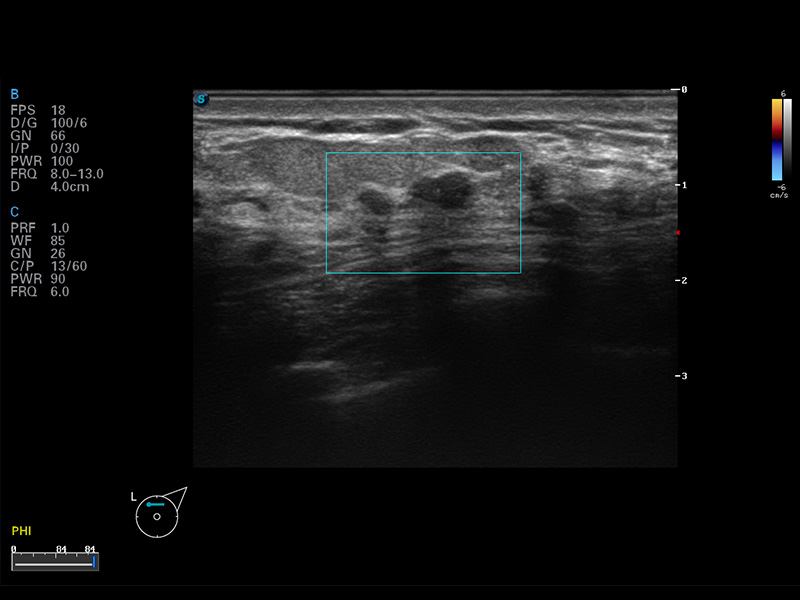

S8 EXP便携式彩色多普勒超声诊断仪是诸侯快讯官网研发的高端全身应用型便携彩超。高通道的VIS平台融合可视化(Visual)、智能化(Intelligent)和人性化(Smart)的特点,配以诸侯快讯官网自主研发生产的探头大家族,使您能够快速、准确的获得病人信息,提高工作效率的同时减轻疲劳。

谐波成像

空间复合成像